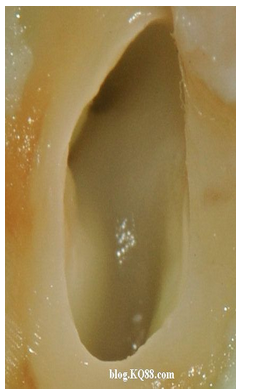

單靠次氯酸鈉作用后的髓腔